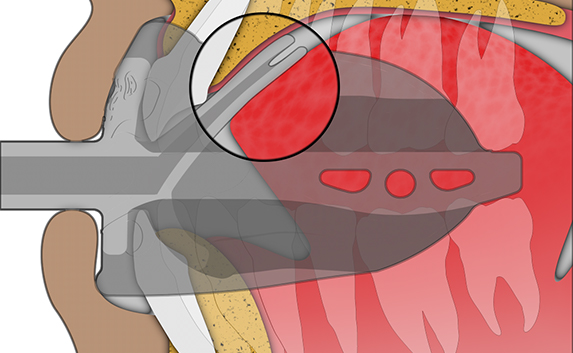

Myosa® for TMJBDS® Stage 1 Hybrid - S1H

Establish a functional airway and permits active exercises

The Myosa® for TMJBDS® S1H is specifically designed for patients who are breathing and disordered sleep (BDS) primary with moderate to severe BDS as indicated by a Breath Hold Time (BHT) of 20 or less. These patients may or may not have TMJ disorders, but due to the severity of their BDS, they require immediate improvement of their airway. The features of the appliance not only work to open the airway, but also allow patients to undertake initial exercising of the lip, tongue and airway muscles. Progress to the S1 when the patient’s BHT reaches 20 seconds or more.